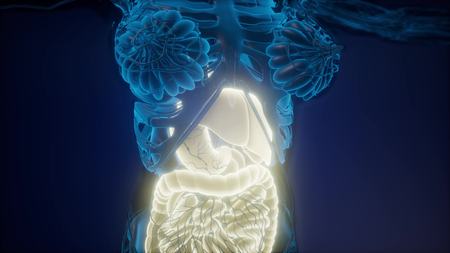

science anatomy scan of human body with visible digestive system

Woman body with digestive system internal organs in x-ray view 3d render

Stomach and intestine with body anterior view

Stomach and intestine with body anterior view